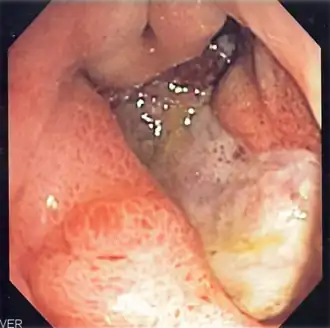

Description de cette image, également commentée ci-après

Ulcère gastrique profond.

La fibroscopie œsogastroduodénale est l’examen de référence. Elle visualise l’ulcère, en détermine la localisation, s’il est isolé ou multiple. Des biopsies sont nécessaires en cas d’ulcère gastrique, pour vérifier l’absence de cancérisation. Les ulcères les plus fréquents sont situés sur la petite courbure de l’estomac et sur le bulbe du duodénum (partie postérieure). On recherchera également une colonisation par l’Helicobacter pylori, très souvent associé à l’ulcère gastroduodénal, et dont l’éradication permettra d’éviter des récidives.